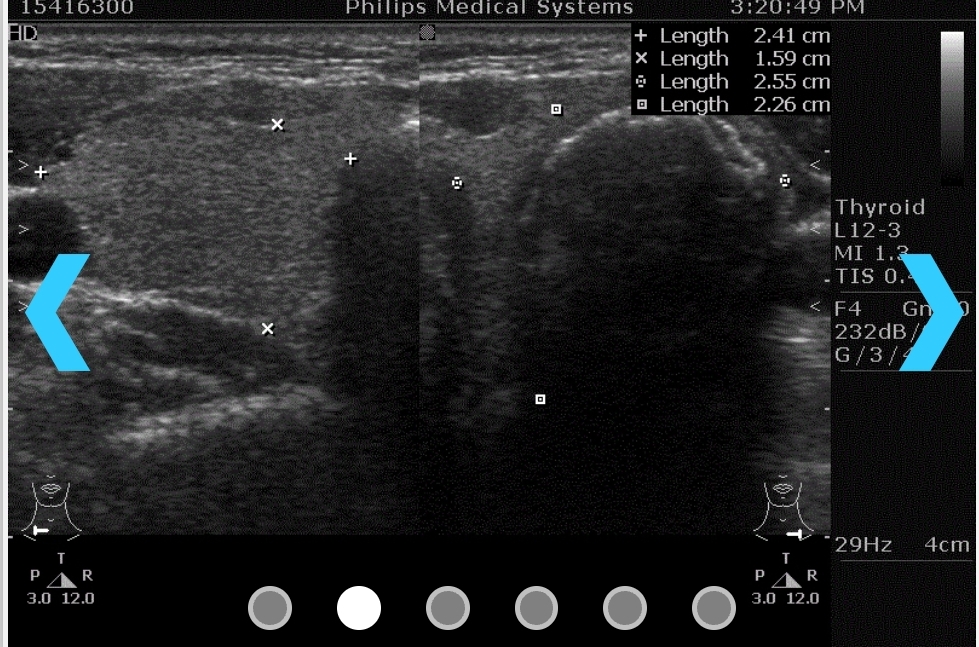

說來也奇怪,按邏輯與習性來說,我應該會選擇腹腔跟子宮這兩部位,但我偏偏莫名的就選了頸部;也因為莫名選了頸部,才照出了頸部有三公分以上的腫瘤。

健檢人員對我說:「這個結節有點大……我覺得你還是去醫院穿刺檢查一下比較好。」

第一次去雙和門診,免不了就是初步的超音波檢查,以及安排進一步的穿刺。

幾個禮拜後,報告出來了,認為是惡性的機率很高。

但穿刺的準確度大約只有75%,是不是惡性必須真正開刀取出那顆腫瘤之後去檢驗才知道。不過醫生也說,就報告的結果、加上超音波照出來的結節形狀來看,十之八九就是癌了。